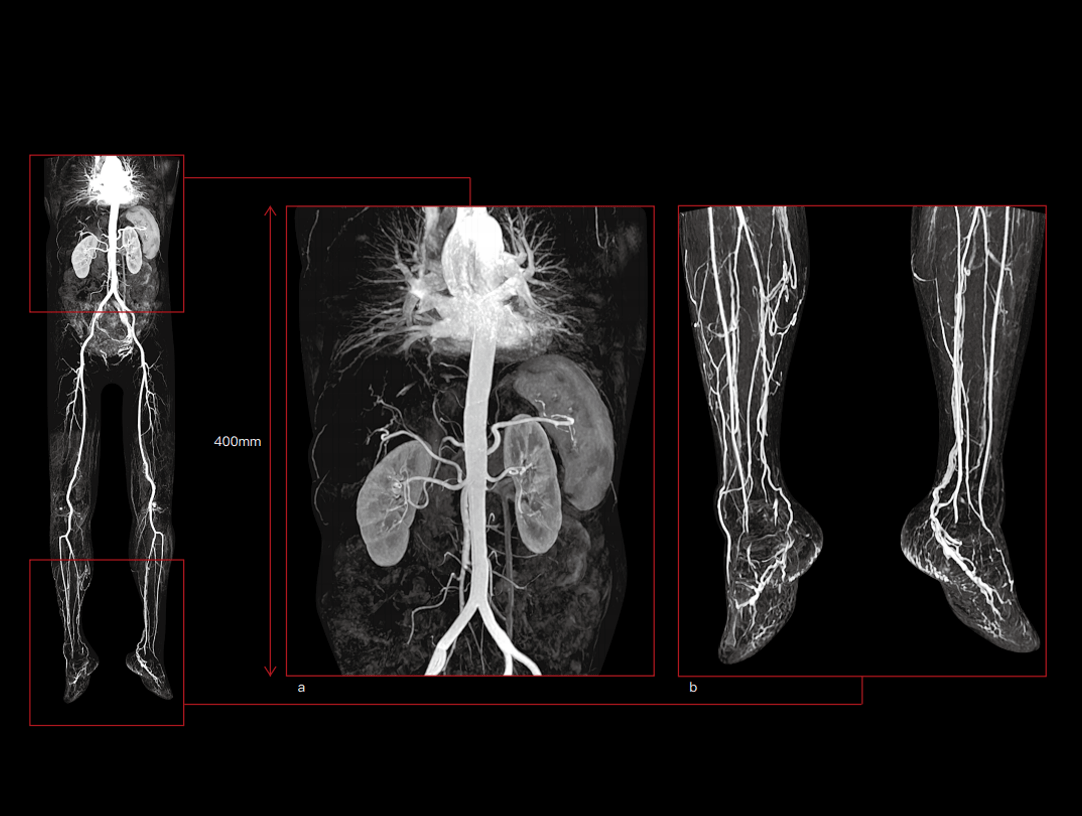

Arterele corpului și ale membrelor inferioare CE-MRA